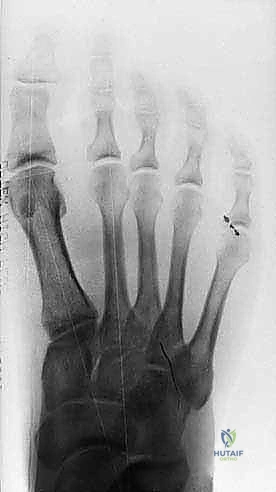

Figure 3: Anteroposterior view of a foot demonstrating a classic bipartite tibial sesamoid.

* Differentiating Bipartite Sesamoid from Fracture: This can be challenging. A fracture line is often sharp and irregular, while a bipartite sesamoid typically has smooth, well-corticated margins. AP radiographs taken in neutral and dorsiflexion can sometimes reveal separation of sesamoid segments in an unstable fracture.

FIG 10 • Preoperative ( A ) and postoperative ( B ) standing radiographs of the foot showing no change in the clinical alignment of the metatarsophalangeal joint after tibial sesamoidectomy. (From Lee S. Technique of isolated tibial sesamoidectomy. Techn Foot Ankle Surg 2004;3:85–90, with permission.)